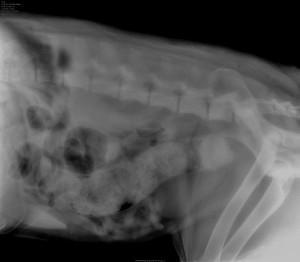

Zelo pomembno je ukrepanje v prvi fazi zaprtja, ko smo opazili, da se žival napenja, vendar ne gre na blato. Takoj je potrebno prenehati s hranjenjem kužka, ga peljati na daljši sprehod in se prepričati, ali res ne more na blato. Kakršnokoli dajanje odvajalnih tablet za ljudi kužku je lahko zelo nevarno, saj delujejo precej drastično, kar lahko  zaradi močnih krčev vodi v predrtje črevesa. [members_only] Kot naravno odvajalo je primerno polnomastno mleko, ki ga živali ponudimo v uživanje. Mleko pri zdravih živalih najpogosteje povzroči drisko in ga veterinarji odsvetujemo, vendar lahko ta odvajalni učinek koristno izrabimo pri zaprtem kužku. V lekarni za ljudi lahko kupimo prorektal sirup, ki se uporablja za ureditev zaprtja pri ljudeh in deluje odvajalno tudi pri živalih. Spada med tako imenovana mehka odvajala, saj ne povzroča močnih krčev črevesja. Če pri vsem omenjenem nismo uspešni in kužek ni šel na blato, vsekakor poiščemo pomoč veterinarja. V ambulanti bomo takšnega kužka najprej rentgensko slikali, da ugotovimo vzrok in stopnjo zaprtja. Če ugotovimo, da gre za čep v samem črevesju in stanje še ni prehudo, bomo kužka klistirali in tako poskusili odmašiti črevo. Za učinkovito klistiranje je pogosto potrebno uporabiti anestezijo živali, saj moramo z gumijasto sondo prodreti   globoko v črevo in tam obilno aplicirati parafinsko olje. Slednje ima nalogo omehčati čep, ki je nastal v črevesju, in naoljiti črevo, da omenjen čep žival lažje izloči. Pogosto pa je potreben urgentni operativni poseg, pri katerem kirurško odstranimo čep iz črevesja in tako vzpostavimo prehodnost. V najhujših primerih, ko zaprtje traja že (pre)dolgo in je črevo že močno propadlo (nekroza črevesja), je potrebna resekcija črevesja, kar pomeni, da del propadlega črevesja izrežemo in zdrave dele ponovno spojimo. Operacija je težka, za pacienta pa zelo stresna in naporna ter tudi prognostično pogosto zelo nehvaležna zaradi zapletenega pooperativnega obdobja. Potrebno je zagotoviti skoraj popolno mirovanje živali zaradi celjenja črevesja, žival se hrani izključno z infuzijo, tudi piti ne sme vsaj dva dni po operaciji. Vsekakor moramo preprečiti kakršnokoli napenjanje in jasno je, da je poseg popolne resekcije črevesja primeren samo za res socializirane kužke, ki sodelujejo pri zdravljenju v pooperativnem obdobju. Za lastnike kužkov je lahko zavajajoč trenutek pri presoji ali gre za zaprtje ali ne. Čeprav gre za zaprtje in celo za popolno zaporo črevesja, lahko kužku med napenjanjem priteče iz analne odprtine kar nekaj tekoče vsebine in tako lastnik pogosto zmotno misli, da ima kužek drisko. Zaradi napenjanja in s tako anamnezo tudi pride k veterinarju. Tudi manj izkušen veterinar lahko v naglici nasede anamnezi lastnika, da ima kužek drisko, se ne prepriča o resničnih vzrokih težav in tako lahko močno zaprt kužek dobi zdravila proti driski, kar je v tem stanju hudo narobe. Tako se zaprtje še poslabša in stopnjuje. Vedno je potrebno stanje temeljito preučiti, uporabiti rentgenski aparat ali ultrazvok za pridobitev diagnoze in ustrezno ukrepati. Vzroki za zaprtje so pogosto lahko tudi zunaj črevesja, v trebušni votlini v obliki raznih tumorjev, ki pritiskajo na črevo in preprečujejo normalno peristaltiko, prav tako je povečana prostata pri samcih pogost vzrok zaprtja. Zelo »banalen vzrok«, predvsem v poletnih vročih dneh, je tudi pomanjkanje sveže pitne vode in briketirana hrana. Kužki, ki se hranijo pretežno z briketi, morajo vedno imeti svežo vodo za pitje, sicer je velika nevarnost zaprtja.